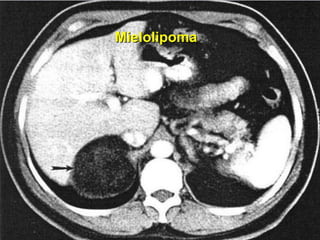

Mielolipoma

PRINCIPAIS INCIDENTALOMAS DA SUPRA-RENAL Siekarizza JL, Bernardino ME, Samaam NA.  Suprarenal mass and its differential diagnosis Urology 18: pp. 625-32, 1981. PATOLOGIA  FREQÜÊNCIA % Adenoma cortical 70 - 94 Adenocarcinoma cortical 0 – 25 Feocromocitoma 0 – 11 Cistos 4 - 22  Mielolipoma 7 – 15 Metástases 0 – 73 Outros  (pseudocistos, granulomas, lipomas, hamartomas) 0 - 10

PRINCIPAIS INCIDENTALOMAS DASUPRA-RENAL Siekarizza JL, Bernardino ME, Samaam NA. Suprarenal mass and its differential diagnosis Urology 18: pp. 625-32, 1981. PATOLOGIA FREQÜÊNCIA % Adenoma cortical 70 - 94 Adenocarcinoma cortical 0 – 25 Feocromocitoma 0 – 11 Cistos 4 - 22 Mielolipoma 7 – 15 Metástases 0 – 73 Outros (pseudocistos, granulomas, lipomas, hamartomas) 0 - 10